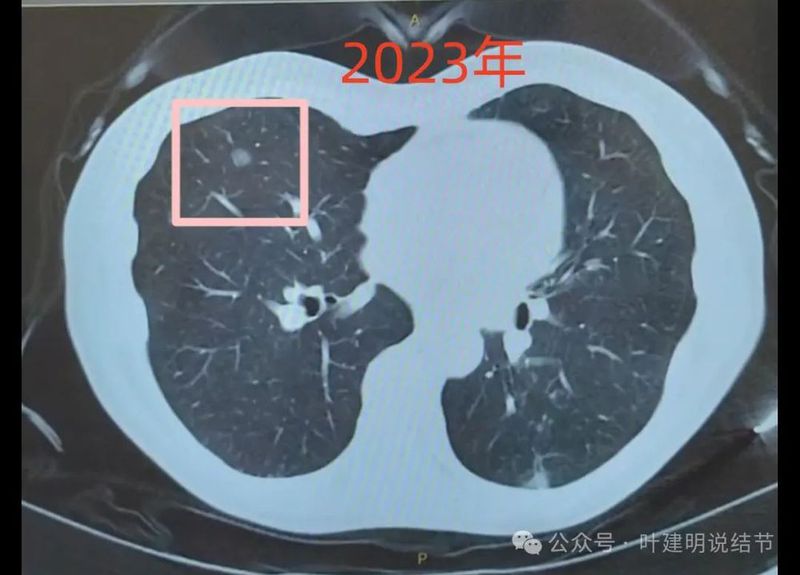

2023年时右肺病灶磨玻璃密度,轮廓与边界清,考虑是原位癌可能性大。

2024年时右侧病灶没有好转,也没有进展,仍考虑原位癌可能性大。左侧2023年也有这处,没有明显变化。

绿色的是今年与去年基本没有明显变化的,而且多中心,斑点状,考虑是慢性炎可能性大;粉色的右侧的是磨玻璃密度,对比持续存在,轮廓与边界清楚,这个要考虑肿瘤范畴的,但以原位癌可能性较大,目前风险仍不高,能随访;红色的是主病灶,今年发现的,但去年的影像上没有,新发现的这种形态上,首先要考虑是炎性的,至少不能先马上考虑恶性。我的想法是先抗炎治疗10-12天,然后过4周左右复查平扫CT,如果有吸收好转,当然证明是炎性的。如果没有好转,并有进展再来考虑穿刺活检也一样的。穿刺若非肿瘤性,不存在导致转移播散之说,如果穿刺明确是恶性,则接下去就要考虑手术的(如果是原发肺癌),所以也不至于就会因穿刺导致转移而影响预后。当然若抗炎无好转,并高度怀疑恶性,位置在边上,单孔局部楔形切了也是可以的,标本量更够,兼具诊断与治疗双重作用。个人想法考虑良性可能性大,建议先抗炎后复查再决定。意见供参考!